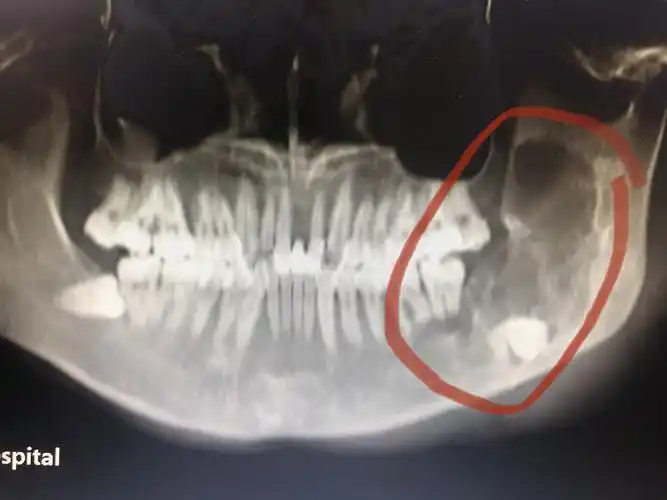

下颌骨骨瘤

巨大下颌骨肿瘤术前右侧位相

下颌骨成釉细胞瘤